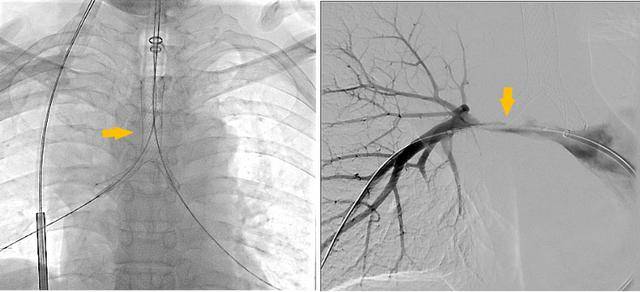

同期置入支架后狭窄明显改善

术后李先生的喘憋症状显著缓解:“那种窒息的恐惧感消失了,我终于能躺下睡个安稳觉了。”为平稳度过危险期,李大爷转至重症医学科接受高级别生命支持与治疗。经过短暂的术后观察,李先生各项生命体征平稳,活动耐量明显改善,顺利出院。